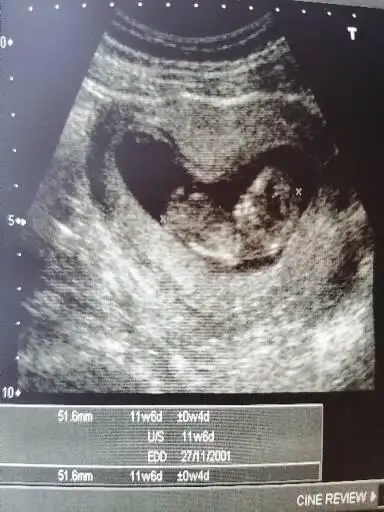

Bana da bakabilir misin ? 12+2

Bir tahmininiz var mı ?